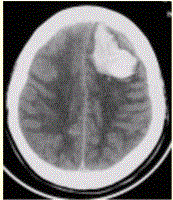

问题 患者男,45岁,突发剧烈头痛伴呕吐30min。既往有高血压病史,平日血压为(190~160)/(100~110)mmHg。查体:右侧肢体肌力Ⅱ级,无颈项强直。CT表现如下图。 有关出血病因,描述错误的是

选项 A.高血压出血常位于基底节区 B.动脉瘤出血多合并以动脉瘤所在部位为主的蛛网膜下腔出血 C.动静脉畸形多可见到等密度迂曲的血管 D.烟雾病多同时出现多处出血和梗死,且多为老年人 E.肿瘤合并出血多在出血周围见到等密度或低于出血的稍高密度瘤体

答案 D